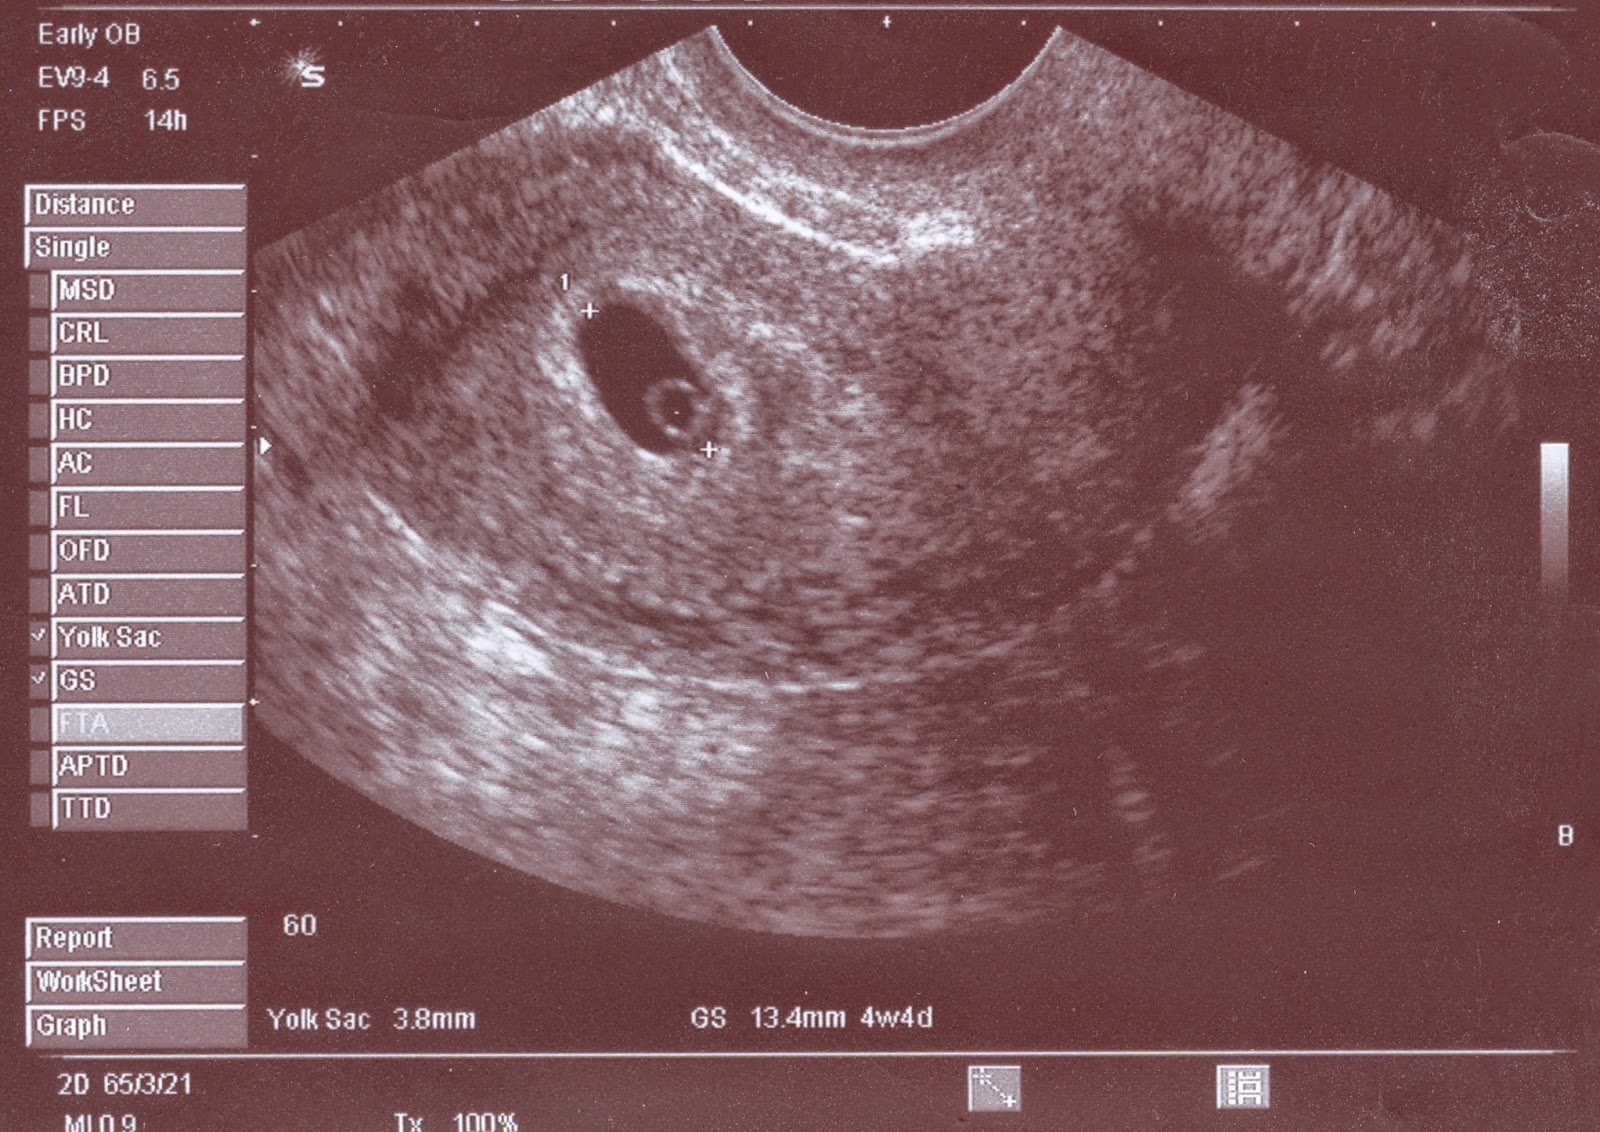

| wczesna ciąża w usg |